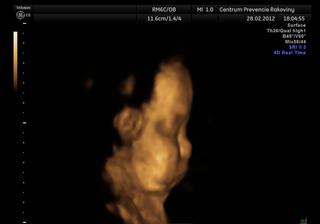

@mirkave my sme v 29 tyzdni vazili cca kilecko..doktor na sone povedal,ze sme trosku mensi,ale v pohode a doktorka povedala,ze sme mooc maly..tak si tiez mozem vybrat 🙂 vcera sme boli na 3d sone aspon trosku sa ukazala..a licka ma ako tatransky svistik, tak urcite podvyzivena nebude 🙂))

Robil mi aj 3d sono, ale mala si dala nohu pred tvar, tak mam fotku ucha 😀